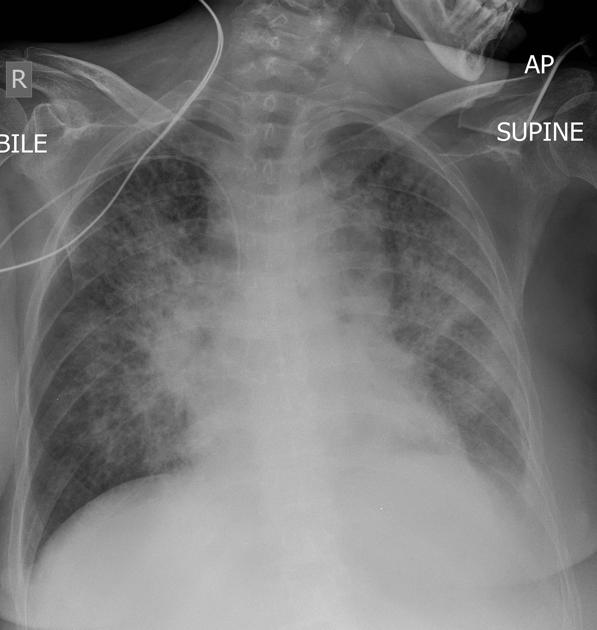

Describe the abnormality demonstrated.

Bilateral perihilar consolidation (Batwing sign) causing loss of visualisation of the right cardiac border and left hemidiaphram (silhouette sign) - pulmonary oedema